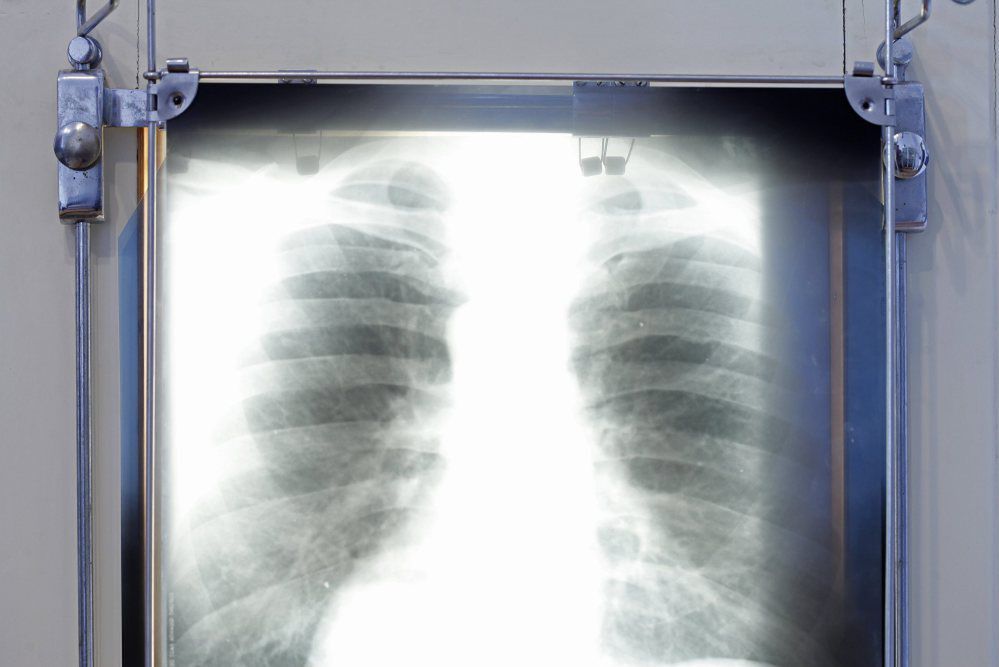

Analizując zdjęcie klatki piersiowej, sztuczna inteligencja potrafi przewidzieć długoterminowe ryzyko zgonu – informuje pismo “JAMA NETWORK OPEN”.

Badania przeprowadził wraz z zespołem dr Michael T. Lu. z Massachusetts General Hospital oraz Harvard Medical School w Bostonie. Sieć neuronowa nazwana CXR-risk, analizująca tysiące zdjęć rentgenowskich klatek piersiowych (projekcja przednio–tylna, AP) zarówno osób palących, jak i niepalących, zdołała na tej podstawie ustalić ryzyko zgonu w dalszej perspektywie.

Badanie dotyczyło bezobjawowych pacjentów w wieku od 55 do 74 lat.

53 proc. osób, u których sztuczna inteligencja przewidywała bardzo wysokie ryzyko zawału serca, raka płuca czy śmierci z innej przyczyny, zmarło w ciągu 12 lat. Natomiast spośród osób zakwalifikowanych przez sieć neuronową jako grupa bardzo niskiego ryzyka zmarło w ciągu 12 lat tylko 4 proc.

Zdaniem autora wykorzystując sztuczną inteligencję można by identyfikować pacjentów z podwyższonym ryzykiem zgonu na podstawie badań, które i tak są już rutynowo wykonywane (zdjęcie rentgenowskie klatki piersiowej to najczęstsze badanie obrazowe). Dzięki ocenie ryzyka zagrożone osoby miałyby szansę podjąć działania profilaktyczne, na przykład zmienić styl życia.

Nawet na zdjęciu rentgenowskim klatki piersiowej zdrowego człowieka często widać subtelne zmiany sylwetki serca czy zwapnienia w ściankach naczyń krwionośnych. Analiza cyfrowego zdjęcia przez sztuczną inteligencję trwa ułamek sekundy.